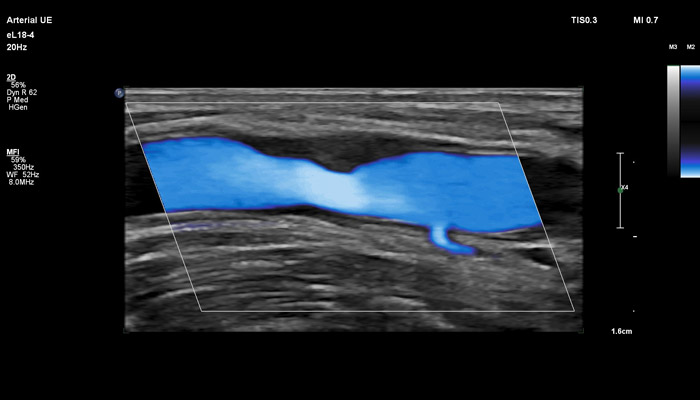

Инновационный датчик eL18-4 работает в частотном диапазоне 2-22МГц, что открывает широкий спектр возможностей его применения в ультразвуковой диагностике. Универсальность датчика позволяет использовать его для комплекса ультразвуковых исследований в таких областях, как: молочная железа (с функцией эластографии сдвиговой волной), поверхностные органы (с функцией эластографии сдвиговой волной), опорно-двигательный аппарат, исследования сосудов (с автоматическим измерением толщины сосудистой стенки), органы брюшной полости, исследования в педиатрии, пренатальная диагностика.

• Исследования сосудов (с автоматическим измерением толщины сосудистой стенки)